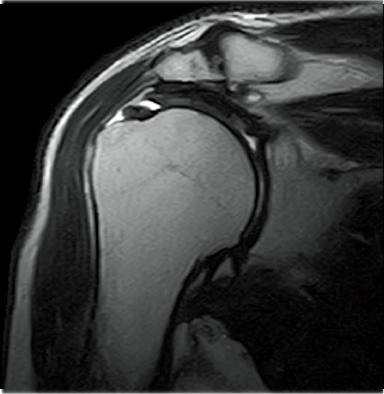

FatSep-T2WI